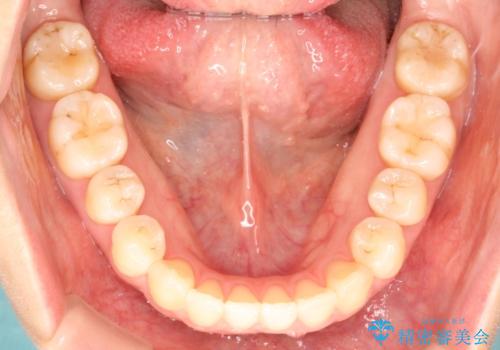

初診時の歯並びの状態としては、上下ともに前歯部に限局した軽度ののがたつき(叢生)がある状態でした。

主に歯列弓の拡大とディスキング(歯と歯の間に隙間を作る処置)を行い叢生を改善しました。